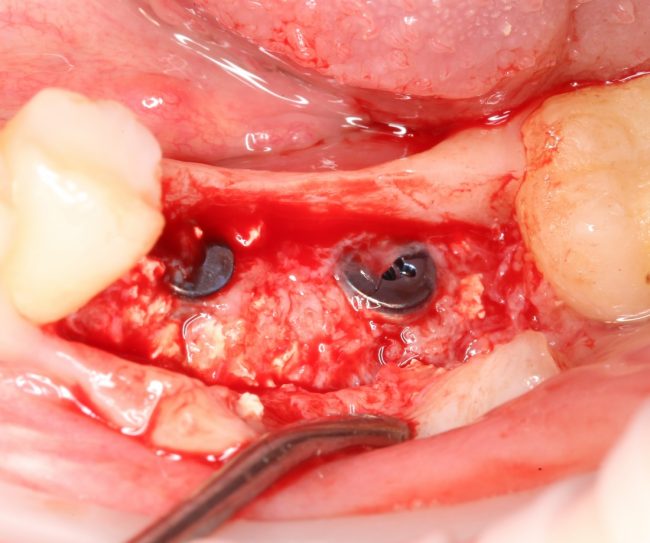

Я постараюсь показать вам, почему из этого:

получается это:

Причём, целесообразно проводить такую манипуляцию даже в случаях, когда мы используем НКР-методы, а не только при аутотрансплантации блоков:

Сделать это не просто, а очень просто: мы просто обрабатываем принимающее ложе, снижая толщину компактной пластинки (вплоть до полного её удаления) и одновременно увеличивая площадь контакта с графтом: